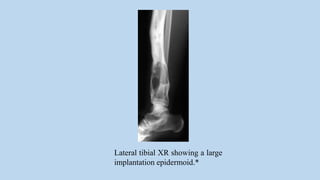

Lateral tibial XR showing a large

implantation epidermoid.*